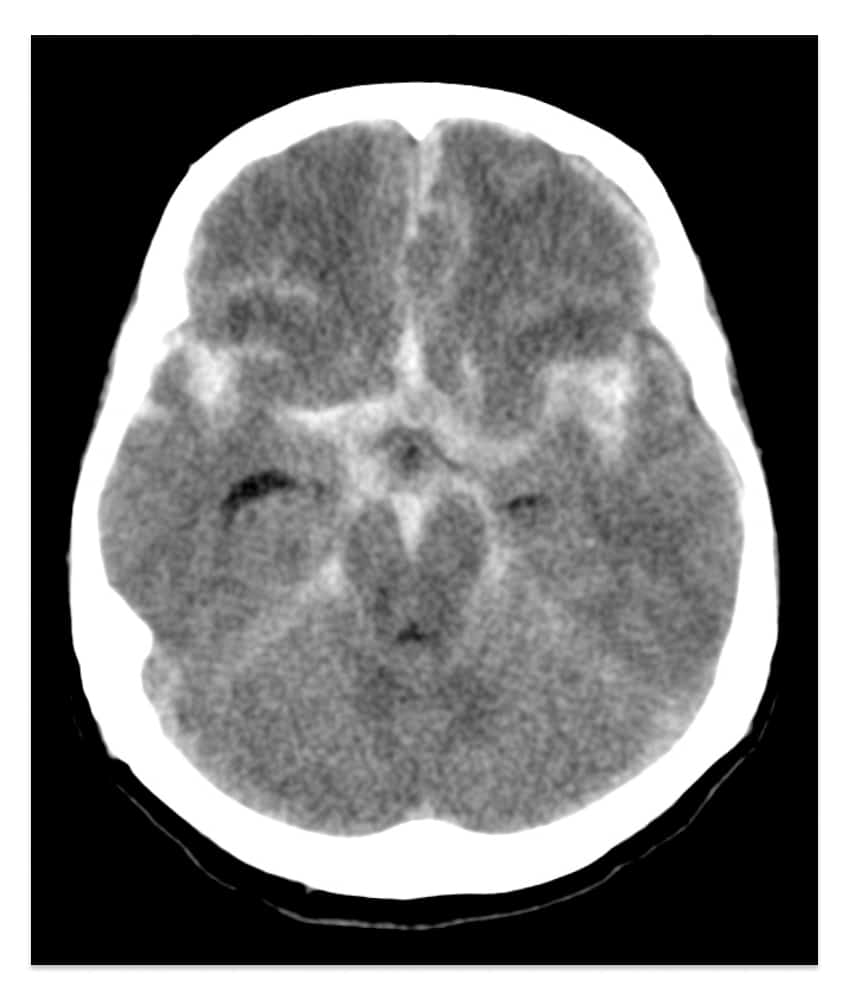

A hemorragia subaracnóidea é facilmente diagnosticada por uma tomografia de crânio (TC) sem contraste na maioria dos casos.

Até 99% dos pacientes que fazem o exame nas primeiras 6 horas da hemorragia, têm o diagnóstico confirmado pela tomografia. Nos raros casos em que o sangue não pôde ser identificado, uma punção lombar para coleta de líquido cefalorraquidiano pode identificar presença de sangue.

Após diagnosticar que houve sangramento subaracnoide, o próximo passo é procurar pelo aneurisma, o que pode ser feito por angiotomografia de crânio (angioTC) ou angiografia cerebral.